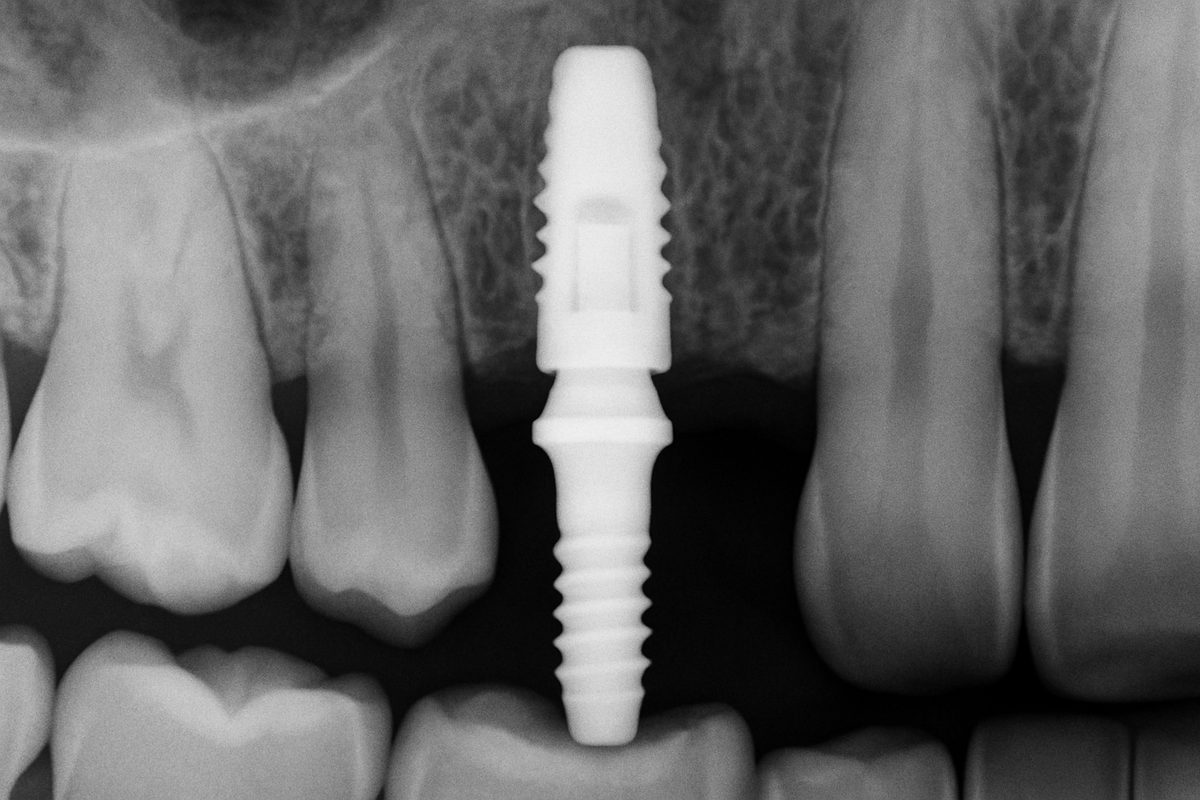

A dental implant has three main parts: the implant post (the root) placed into the jawbone, the abutment that connects the post to the tooth, and the crown or prosthesis that looks like the visible tooth. Unlike bridges or removable dentures, implants fuse to bone (osseointegration) and act like a natural tooth root. That gives more stability, better chewing, and helps prevent bone loss over time.

Expect a review of your medical history, digital scans or X-rays, and a clear treatment plan. Many practices use 3D imaging to plan exact implant placement.

The implant post is placed into the jawbone during a minor surgical visit. Healing (osseointegration) typically takes a few months as the bone bonds to the implant.